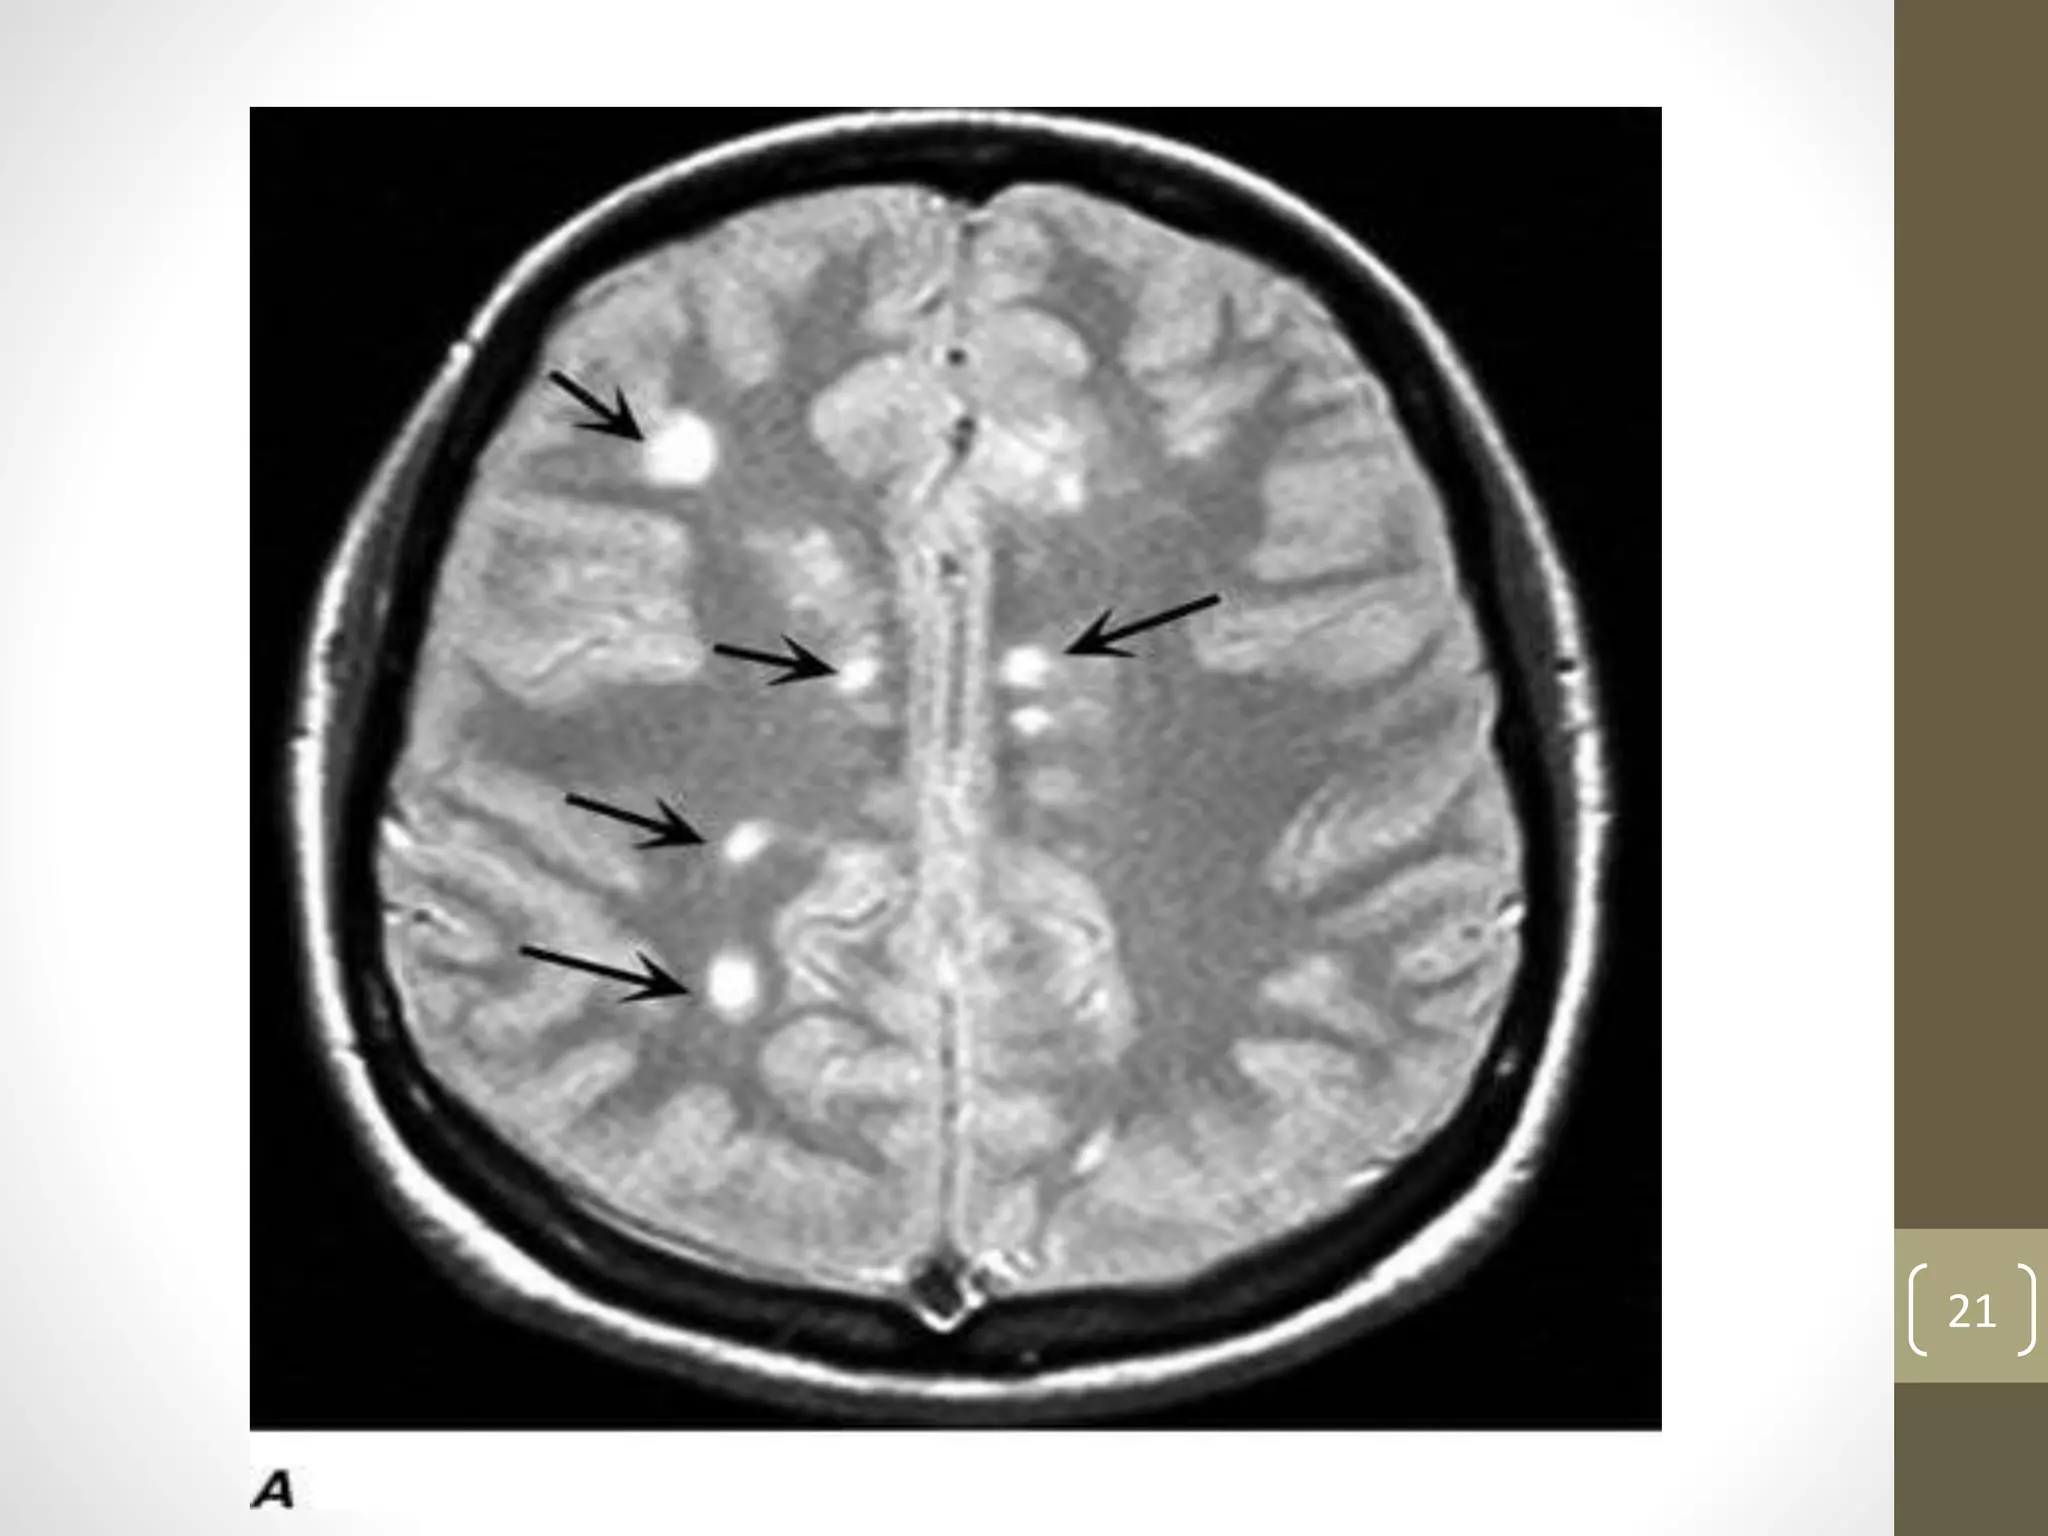

MRI:

• Characteristic abnormalities are found in 95% of patients

• An increase in vascular permeability from a breakdown of the

BBB is detected by leakage of intravenous gadolinium (Gd)

into the parenchyma. Such leakage occurs early in the

development of an MS lesion and serves as a useful marker of

inflammation. Gd-enhancement persists for up to 3 months.

• Newer MRI measures such as brain atrophy, magnetization

transfer ratio (MTR) imaging and proton magnetic resonance

spectroscopic imaging (MRSI) may ultimately serve as

surrogate markers of clinical disability.

• For example, MRSI can quantitate molecules such as N-acetyl

aspartate (NAA), which is a marker of axonal integrity, and

MTR may be able to distinguish demyelination from edema.